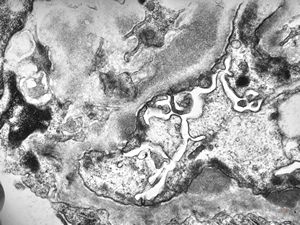

F,18y. | type I membranoproliferative glomerulonephritis

type I membranoproliferative glomerulonephritis